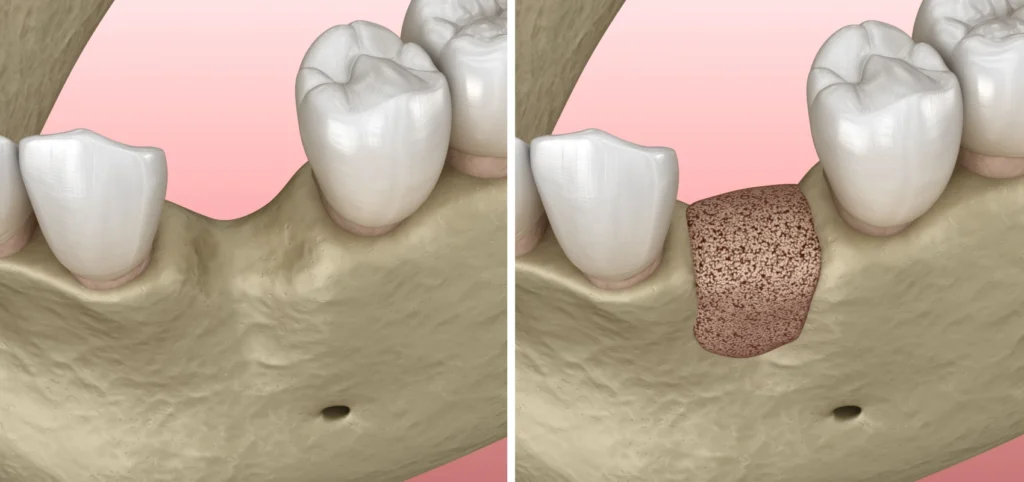

Le traitement de la parodontite commence généralement par un nettoyage en profondeur des gencives et des racines des dents. Cela permet d’éliminer la plaque dentaire et le tartre, qui sont responsables de l’infection. Ce processus se compose de deux étapes : le détartrage et le surfaçage radiculaire.

Détartrage en Débridement radiculaire

Le détartrage est une procédure essentielle pour traiter la parodontite. Elle consiste à retirer la plaque dentaire et le tartre, qui s’accumulent sous et au-dessus de la ligne des gencives. La plaque dentaire se forme à partir des résidus alimentaires et des bactéries. Si elle n’est pas éliminée, elle se transforme en tartre, plus difficile à retirer. Le détartrage permet de réduire l’inflammation des gencives et d’éviter l’aggravation de l’infection. Cela aide également à restaurer la santé des gencives et à prévenir la perte de dents.